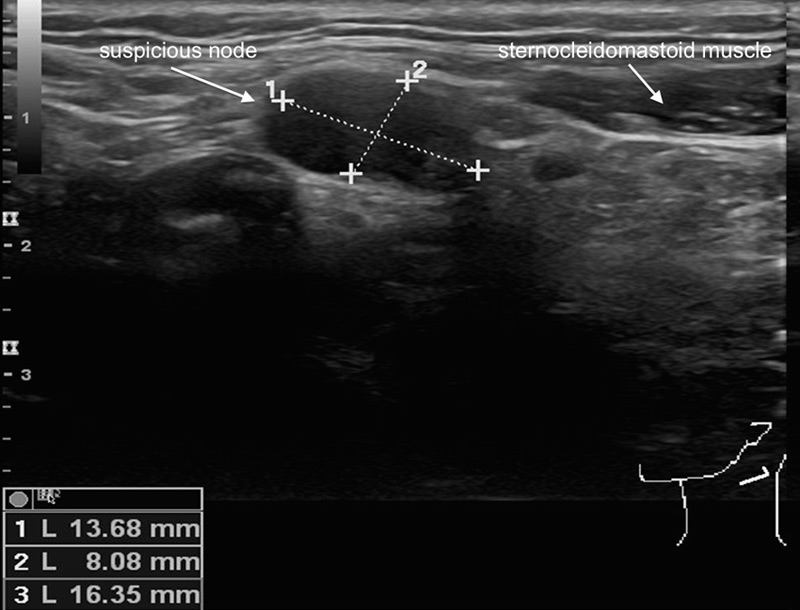

Figure 1

Sonographic appearance of a suspicious lymph node on palpation in level II left from a patient with a small squamous cell carcinoma of the right lateral tongue. The absence of an echogenic hilus, the size of more than 1.5cm and the shape of the lymph node renders it sonographically suspicious. The cytology result after ultrasound-guided fine needle aspiration confirms the presence of a contralateral positive node.

Regional lymphatic involvement for patients suffering from HNSCC is the strongest prognostic factor in these patients [22]. Patients with no nodal involvement count for a 5–year survival of 63% to 86%, whereas 5–year survival rates of 20–36% for patients with lymph node metastases are noted [23]. Clinical examination and appropriate imaging leads to optimal clinical staging and classification of the neck, which has important impact on the treatment decision regarding surgical and non-surgical treatment options. The staging options for patients with a clinical negative neck are manifold and there is a lack of prospective comparative studies in homogeneous patient cohorts with uniform inclusion criteria for the evaluation of the most accurate imaging modality- Ultrasound-guided fine needle aspiration cytology (USgFNAC) seems to correlate best with the exact histologic staging (fig. 1) [24]. There is a correlated sensitivity regarding this technique with the investigator’s skills [25]. However, there seems to be an increasing number of head and neck Surgeons performing neck ultrasounds by themselves. Most centres throughout the world still perform a CT scan if ultrasound is not available in an office-based set up. Since the primary tumour cannot be assessed using ultrasound there is no doubt performing a CT scan for staging reasons is arguable. However, as stated above, maybe the primary will better be assessed by an MRI. Constrast-enhanced CT and MRI are the methods of choice to evaluate the primary tumour, but their accuracy for nodal metastases is discussed in recent reports [26]. Therefore the authors advocate performing an ultrasound of the neck, and, if necessary, an USgFNAC, for staging the clinical N0 neck. In surgical cases patients with a clinical N0–neck should be offered minimally invasive sentinel node biopsy (SNB) [27] or risk-level-based elective neck dissections (ENDs) [28] for most accurate staging purposes. There is a different algorithm if patients present with clinically positive neck involvement. More than a single node is involved (N2b or N2c) or an involved lymph node of more than 3cm in maximum diameter (N2a or N3) is related with a higher risk of distant metastases, and therefore, 18F-FDG-PET/CT is indicated to exclude such [29]. Nevertheless, because of its low costs and its additional value for the assessment of the neck, a neck ultrasound will be added at our institution. For surgical candidates, final staging will be completed after histological assessment of the tissue specimen obtained from the neck dissection specimen [30]. On the other hand, in patients who receive a primary (chemo) radiation, the staging of the neck is ‘solely’ based on imaging. In these cases, the authors advocate performing metabolic imaging for two reasons: First, the metabolic information retrieved from a 18F-FDG-PET/CT can be further used for dose-painting in the planning phase, and second, treatment response after therapy can be assessed by using the metabolic part of the multimodality imaging [31, 32].